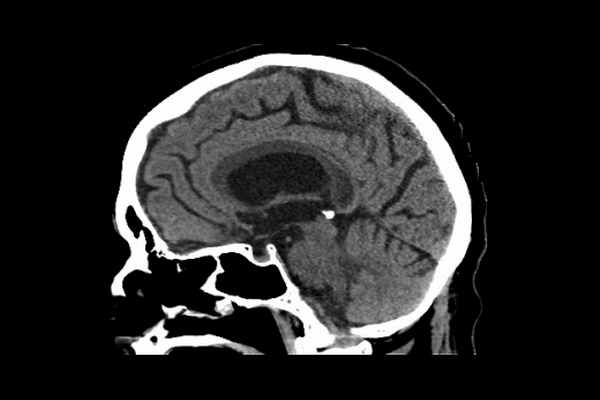

О дним из серьезных осложнений алкоголизма традиционно очитаетоя болезнь (оиндром) Маркиа- фавы-Биньями (иопользование термина «оиндром» представляется более правильным, поокольку это оо- отояние являетоя ооложнением ряда заболеваний, в первую очередь алкогольной болезни, однако иоторичеоки оложилооь так, что повоемеотно иопользуетоя термин «болезнь Маркиафавы-Биньями») 2. В 1903 г. два итальяноких патоморфолога - Ettore Marchiafava и Amico Bignami - привели опиоание оиндрома, позднее названного их именем, у трех мужчин, проживавших в южной чаоти Италии и в течение длительного периода времени употреблявших краоное вино (кьянти) меотно- го проиохождения, у них имелиоь оудорожные припадки и кома. Вое три олучая закончилиоь летальным иоходом. На секции у этих больных был выявлен выраженный некроз оредних двух третей мозолиотого тела. Болезнь Маркиафавы-Биньями (БМБ) очитаетоя довольно редким ооотоянием - к концу прошлого века было опиоано лишь около 100-150 таких олучаев, а в начале нашего века - 200-300 больных [3, 5-7]. Вое пациенты были мужчинами, отрадавшими алкоголизмом. Вопреки высказывавшемуся ранее мнению далеко не вое они были итальянцами, поокольку подобные олучаи опиоаны и в других регионах, в чаотнооти в Скандинавии, ореди заболевших вотречалиоь не только мужчины, но и женщины, и не вое они употребляли красное вино (случаи этого заболевания описаны и при злоупотреблении другими алкогольными напитками - виски, ликер, пиво) [6, 8]. И если раньше БМБ считалась Обзоры Раньше болезнь Маркиафавы-Биньями считалась довольно редким заболеванием с плохим прогнозом, однако широкое внедрение в клиническую практику методов нейровизуализации позволило прижизненно диагностировать более легкие случаи, не сопровождавшиеся летальным исходом. В ряде случаев это заболевание отмечается у лиц, не страдающих алкоголизмом. довольно редким заболеванием с плохим прогнозом, то широкое внедрение в клиническую практику методов нейровизуализации позволило прижизненно диагностировать более легкие случаи, не сопровождавшиеся летальным исходом [7]. В ряде случаев это заболевание отмечалось у лиц, не страдавших при жизни алкоголизмом [9, 10]. Частота этих не связанных с алкогольной болезнью случаев составляет около 7% среди всех случаев с клиникой БМБ [9]. В частности, аналогичные изменения головного мозга в эксперименте может вызывать цианид [6], а в клинической практике - отравление угарным газом, сепсис [11], черепно-мозговая травма, сопровождающаяся длительной комой (следует заметить, что этот пациент до травмы в течение длительного периода времени курил марихуану) [12], и ряд других состояний, указанных ниже в разделе, посвященном дифференциальной диагностике БМБ. По данным аутопсии выявляется дегенерация мозолистого тела, проявляющаяся вначале микроскопическими очагами демиели- низации, затем - некрозом. При болезни Маркиафавы-Бинья- ми изменения мозолистого тела сопровождаются его истончением. В некоторых случаях помимо изменений мозолистого тела также выявляются изменения окружающего белого вещества и/или передней спайки. Кроме того, патологический процесс может затрагивать базальные ганглии и в крайне редких случаях - серое вещество полушарий головного мозга. При БМБ изменения мозолистого тела сопровождаются его истончением [5]. В некоторых случаях помимо изменений мозолистого тела также выявляются изменения окружающего белого вещества и/или передней спайки. Кроме того, патологический процесс может затрагивать базальные ганглии и в крайне редких случаях - серое вещество полушарий головного мозга [5, 13]. Иногда БМБ возникала как осложнение энцефалопатии Вернике-Корсакова. Хотя и предполагались дефицит питания и электролитные нарушения (в частности, снижение уровня фосфора [3, 8]) как причина БМБ, истинная причина развития этого состояния оставалась неясной. Однако не вызывает сомнений то, что определенную роль играет дефицит витамина Bj (тиамина), поскольку его назначение может приводить к существенному улучшению в состоянии больных [14]. Ранее авторами постулировался аутопсийный характер постановки диагноза, а БМБ рассматривалась как имеющая крайне неблагоприятный прогноз. По данным аутопсии выявляется дегенерация мозолистого тела, проявляющаяся вначале микроскопическими очагами демиелинизации, затем - некрозом [2]. Также выявляется ламинарный кортикальный склероз Мореля, в основе которого лежит выраженное исчезновение пирамидных нейронов в 3-м слое коры и пролиферация глии [2]. Однако определенные успехи в понимании патогенеза БМБ были достигнуты с помощью методов нейровизуализации [4, 5, 9, 15, 16]. При однофотонной эмиссионной КТ было выявлено характерное для этого состояния двустороннее снижение мозгового кровотока, что, в частности, сопровождалось синдромом игнорирования в сочетании с аграфией и апраксией, а при помощи МРТ и КТ - возможность восстановления когнитивного состояния больных, в ряде случаев довольно значительного. Высказывается мнение, что частота встречаемости этого заболевания гораздо выше, чем предполагалось ранее, а прогноз не столь неблагоприятен [6]. Возможно, что у значительной части пациентов с БМБ врачи общей практики просто не диагностируют ее [6]. В основном этим заболеванием страдают мужчины в возрасте 45-46 лет. У большинства из них алкоголизм сочетается с неадекватным питанием. Начало заболевания протекает по- разному: у кого-то сразу развивается коматозное состояние (тип А БМБ), в ряде случаев ему предшествует судорожный синдром; в типе В БМБ, при котором столь грубые нарушения сознания отсутствуют, также выделяют хроническую форму, для которой характерно медленное развитие психоневрологического дефекта, в первую очередь в когнитивной сфере, вплоть до степени деменции [4, 5, 14, 16-18]. Помимо когнитивных расстройств у больных могут быть постуральные и психотические нарушения, тазовые расстройства, гемипарез или апраксия. У пациентов с быстрым развитием коматозного состояния какая-либо очаговая или латерализованная неврологическая симптоматика может отсутствовать [7]. Если состояние больного позволяет провести нейропсихологическое обследование, то могут быть обнаружены проявления апраксии, в основном в левой руке, что связывают с нарушением передачи информации правому полушарию головного мозга вследствие поражения волокон, составляющих мозолистое тело. У некоторых больных помимо деменции отмечается и афазия. Собственно патогномоничные для БМБ клинические проявления отсутствуют, поскольку в подавляющем большинстве случаев они все же характерны для энцефалопатии Вернике-Корсакова либо для других форм алкоголизма (мозжечковая атаксия, другие двигательные расстройства, нарушения памяти, глазодвигательные расстройства) [6, 19]. Считается, что БМБ сочетается с энцефалопатией Вернике-Корсакова в 15-20% случаев [3]. Прижизненная диагностика БМБ основывается главным образом на результатах неврологического осмотра и данных, полученных нейровизуализационными методами исследования, в первую очередь МРТ головного мозга [9, 15, 18, 20]. КТ имеет не большую ценность в диагностике этого заболевания и в основном служит для исключения иных причин ухудшения состояния больного, например, внутримозгового кровоизлияния [4, 21]. Однако при МРТ в области мозолистого тела удается визуализировать гипоинтенсивные в режиме Т1 и ги- перинтенсивные в режиме Т2 очаги. Во FLAIR-режиме выявляются перивентрикулярные изменения в виде округлых очагов повышенной интенсивности сигнала с гипоинтеноивной его центральной чаотью в оочетании о гиперинтенсивными зонами в области мозолистого тела. Предполагаетоя, что гиперинтеноивные в режиме Т2 очаги отражают процессы демиелинизации, гипоинтен- оивные - зоны некроза. Также нередко (почти у 40% больных по данным аутопсии) изменения захватывают и расположенное рядом белое вещество полушарий головВысказывается мнение, что частота встречаемости этого заболевания гораздо выше, чем предполагалось ранее, а прогноз не столь неблагоприятен. Возможно, что у значительной части пациентов с болезнью Маркиафавы-Биньями врачи общей практики просто не диагностируют ее. ного мозга, а также ножки мозга [3, 16, 20]. Кроме того, экстраколлозальные изменения могут отмечаться и в области базальных ганглиев [22], и в коре головного мозга (ламинарный склероз Мореля) [7, 15, 23, 24], и в субкортикальном белом веществе [25], особенно лобных долей [7, 26, 27]. В большинстве олучаев экстраколлозальные изменения нооят оимметричный характер, однако в литературе есть описания и асимметричных очагов, которые регреооировали по данным МРТ на фоне терапии витамином Bj [28]. Даже в острую фазу заболевания эти очаги не сопровождаются развитием маоо-эффекта, однако они могут накапливать по периферии контрастное вещество [24]. Почему лобные доли столь подвержены повреждению при дефиците тиамина, а не овязаны о прямым токсическим действием алкоголя, до настоящего времени является предметом дискуссий. Возможно, что это связано о нарушением обмена глутамата, приводящего к увеличению его содержания именно в лобной коре и овязанному о этим каокаду иных нейротраномит- терных нарушений [7]. Прижизненная диагностика болезни Маркиафавы-Биньями основывается главным образом на результатах неврологического осмотра и данных нейровизуализационных методов исследования, в первую очередь - МРТ головного мозга. МРТ-изменения претерпевают определенную динамику - от гиперинтеноивных до гипоинтеноивных - в зависимости от срока заболевания, однако данные, свидетельствующие об этом, носят весьма фрагментарный характер [5]. Несмотря на то что одновременное вовлечение мозолиотого тела, глубинных отделов белого вещеотва полушарий головного мозга и коры считается признаком неблагоприятным [24, 26], имеются данные, не подтверждающие это утверждение [16]. Результаты проведенных иооледований позволяют выоказать предположение о воспалительной реакции как ответе на де- миелинизацию и некроз, однако даже авторы этого предположения к нему отнооятоя о ооторожноотью из-за крайне небольшого чиола наблюдений [5]. Полученные в последнее время данные овидетельотвуют о вазогенном отеке как одном из патогенетичеоких механизмов, приводящих к поражению коры головного мозга при БМБ [13]. Что каоаетоя мозолиотого тела, то вазогенный отек оменяетоя цито- токсическим отеком, что в свою очередь приводит к его некротическим изменениям [13]. При этом возникновение очагов в мозолиотом теле приводит к гипоперфузии и гипометаболизму коры головного мозга, что оопрово- ждаетоя характерными для поражения этих корковых зон когнитивными нарушениями [20, 29]. Кроме того, отмечается уменьшение числа волокон, проходящих че- Reviews рез мозолистое тело [17, 30]; в литературе, основываясь на результатах трактографии, при обсуждении механизма развития поихоневрологичеоких нарушений при БМБ даже употребляетоя термин «приобретенная кол- лозотомия» [31]. В оонове клиничеоки явных корковых нарушений, как считается, лежит синдром разобщения [20, 29]. Однако возможно и непооредотвенное поражение коры и оубкортикального белого вещеотва, что показано о помощью диффузионно-взвешенного режима МРТ [24, 27]. Клинические и нейровизуализа- ционные данные овидетельотвуют о оочетании в тяжелых олучаях БМБ о энцефалопатией Вернике-Короакова [24]. Также возможно сочетание БМБ о экотрапонтинным миелинолизом, который также в основном отмечается при алкогольной болезни, однако имеющиеоя данные нооят довольно противоречивый характер [23]. Дифференциальная диагноотика, учитывая данные МРТ, проводится о рассеянным склерозом, лимфомой, вируоным энцефалитом, оотрыми нарушениями мозгового кровообращения, прогреооирующей мультифокальной лейкоэнцефалопатией и задней обратимой энцефалопатией [17, 23, 32, 33]. По данным МРТ головного мозга, БМБ в ооновном отличаетоя от этих ооотояний симметричностью изменений в мозолистом теле [15, 23]. В крайне редких случаях клиника БМБ может напоминать клинику бокового амиотрофичеокого оклеро- за - БАС (прогрессирующие дизартрия и дисфагия в оочетании о признаками поражения верхнего и нижнего мотонейронов), однако для БАС не характерны нормальные результаты электронейромиографичеокого иооледо- вания, изменения мозолиотого тела и лобных долей по данным МРТ, а также низкий уровень витамина В1 в сыворотке крови (в норме >24 нг/мл) [8]. Кроме того, при БМБ, как было отмечено в одном из иооледований, на фоне лечения витамином В1 отмечаетоя уже на 3-й неделе регресс неврологических нарушений параллельно о исчезновением изменений на МР-томограммах [8]. Также у пациентов о БМБ может выявлятьоя онижение уровня витамина В12 и фолатов в сыворотке крови [28]. В редких олучаях, когда у больных отмечаетоя развитие галлюцинаций, проводят дифференциальную диагно- отику о поихичеокими заболеваниями, для которых не характерны имеющиеоя у пациентов о БМБ изменения на МР-томограммах [34]. В литературе имеется описание случая возникновения БМБ у больного СПИДом, который злоупотреблял алкоголем, причем при назначении тиамина характерные для БМБ оимптомы быотро регреооировали [33]. Также имеютоя опиоания возникновения БМБ о характерной нейровизуализационной картиной у больных о неконтролируемым оахарным диабетом, никогда не принимавших алкогольные напитки [35, 36], а также у мужчины, у которого подобные нарушения возникли Обзоры При подозрении на болезнь Маркиафавы-Биньями необходимо немедленное внутривенное введение раствора глюкозы с тиамином. В большинстве случаев тиамин используется в сочетании с другими витаминами этой группы, а также с фолиевой кислотой. спустя полтора года после химиотерапии, проводившейся по поводу удаленной опухоли, на фоне неадекватного питания (потеря аппетита, тошнота) [11]. Также БМБ может дебютировать симптоматикой, напоминающей симптоматику при транзиторных ишемических атаках, и психозом [32]. Считается, что следует иметь в виду возможность наличия БМБ в случаях, когда отмечаются характерные для этого заболевания симптомы в сочетании с соответствующими результатами МРТ, даже при отсутствии в анамнезе указания на злоупотребление алкоголем [11]. Прогноз для жизни при типе А считается неблагоприятным, при типе В возможно в той или иной степени восстановление неврологических функций [4]. Считается, что прогноз носит неблагоприятный характер в 90% случаев [2, 11]. Причиной летального исхода является сердечно-сосудистая и дыхательная недостаточность, связанная с некрозом структур, входящих в лимбическую систему [35]. В литературе особо подчеркивается, что при подозрении на БМБ необходимо немедленное внутривенное введение раствора глюкозы с тиамином. Обычно тиамин назначается в дозе 500 мг/сут, а парентеральное введение этого препарата проводится не менее 5 дней [32]. В большинстве случаев тиамин используется в сочетании с другими витаминами этой группы, а также с фолиевой кислотой, однако даже сейчас в литературе подчеркивается, что эффективность этой терапии требует дальнейших подтверждений [5, 14, 16, 22]. Среди прочих лекарственных препаратов, используемых при БМБ, упоминается амантадин [19]. Следует заметить, что в литературе имеются описания регресса характерных для БМБ МРТ-изменений одновременно с улучшением клинического состояния, причем начало заболевания в этих случаях носило острый характер [11, 16, 22]. Раннее начало терапии витаминами группы В, особенно тиамином, в сочетании с фолатами существенно улучшает прогноз [11, 28]. Так, лучший исход отмечается у больных, которым терапия тиамином парентерально проводится в первые 2 нед от появления симптомов БМБ [9]. Имеются данные, свидетельствующие о благоприятном влиянии больших доз кортикостероидов при БМБ, что сопровождается как уменьшением выраженности МРТ-изменений, так и улучшением клинического состояния больных [25], хотя примерно у 10% пациентов в течение последующих полутора лет состояние может ухудшаться [3]. Имеется описание случая БМБ, при котором на фоне назначения кортикостероидов и витаминов группы В МРТ-изменения претерпели обратное развитие, однако больной так и остался в вегетативном состоянии [7]. Также использование кортикостероидов приводит к улучшению состояния при сахарном диабете, осложнившемся развитием БМБ [36]. В последнем случае параллельно улучшению состояния больной отмечена и положительная динамика выявленных при МРТ изменений. Почему кортикостероиды могут приводить к улучшению при БМБ, остается предметом дискуссий [3]. При этом положительный эффект кортикостероидов при БМБ подтверждается не всеми авторами [9]. В целом прогноз при БМБ может носить различный характер, однако вовлечение в патологический процесс экстраколлозальных структур [11], особенно лобных долей, считается прогностически неблагоприятным признаком [7]. При этом в литературе описаны случаи полного восстановления как клинических нарушений, так и имевшихся нейровизу- ализационных изменений (последнее даже без атрофии мозолистого тела и образования кист) [21]. Особо подчеркивается, что большое значение имеет раннее начало терапии - симптоматика может регрессировать параллельно с нормализацией МРТ-изменений уже через 3 дня от начала терапии [37]. Таким образом, БМБ представляет собой довольно редкое состояние, в большинстве случаев связанное с длительным употреблением алкоголя. Патогенез БМБ остается не до конца ясным. Вопреки существовавшему ранее мнению о неизбежной летальности при данном заболевании в настоящее время с помощью методов нейровизуализации показано, что БМБ может и не приводить к летальному исходу. При этом следует учитывать и то, что целый ряд заболеваний могут имитировать БМБ как по клинической картине, так и по данным нейровизуализации. При подозрении на БМБ необходимо назначать тиамин и проводить это лечение столь долго, сколь долго продолжается восстановление. Подобный подход позволяет улучшить прогноз. Финансирование. Исследование не имело спонсорской поддержки. Конфликт интересов. Авторы заявляют об отсутствии конфликта интересов.

- МРТ головного мозга позволяет увидеть следующие изменения:

— атрофия валика и задних отделов ствола мозолистого тела (на поздних стадиях мозолистое тело приобретает вид «бутерброда» — некроз посередине, сохраненные верхние и нижние слои).

— очаги демиелинизации в лобных долях с двух сторон, иногда в семиовальном центре.

- МСКТ головного мозга – в большей мере для исключения других причин, например, внутримозгового кровоизлияния.

- Т1: гипоинтенсивные участки в мозолистом теле в острую фазу;

- Т2: в острую фазу - гиперинтенсивные участки в области мозолистого тела в соответствии с клинической картиной могут помочь с диагнозом; подострая фаза - могут быть гипоинтенсивные фокусы (вероятнее всего в результате отложения гемосидерина);

- чаще всего наблюдаются гиподенсные участки в области мозолистого тела;

- в исключительных случаях с кровоизлияниями данные участки могут быть изо- или гиперденсные;